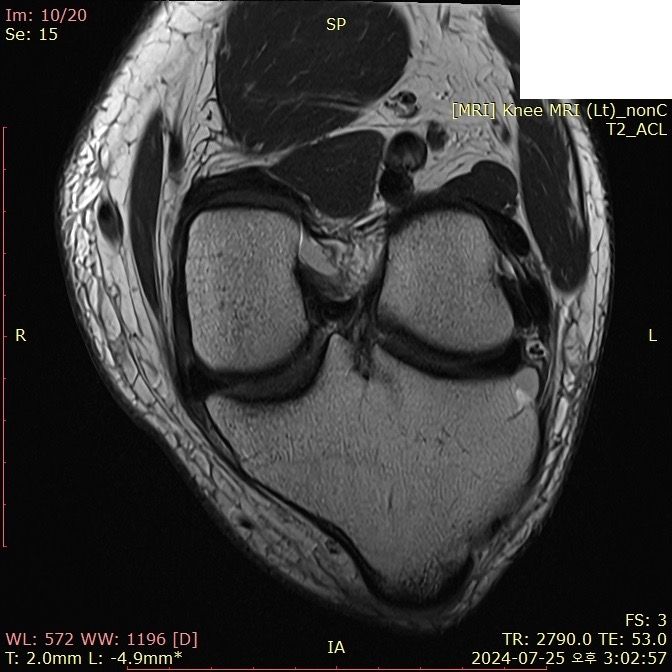

무릎 ACL(전방십자인대) 확인 부탁드려요

아스팔트에 무릎을 부딪쳐 심하게 부어서 mri 찍어봤는데 슬개골 비변위성 골절 판독 받은 건 기억 나는데, 인대는 기억이 잘 안나서 여쭤 봅니다..

전방십자인대 괜찮은가요...??ㅠㅠ

• 3번 째 사진